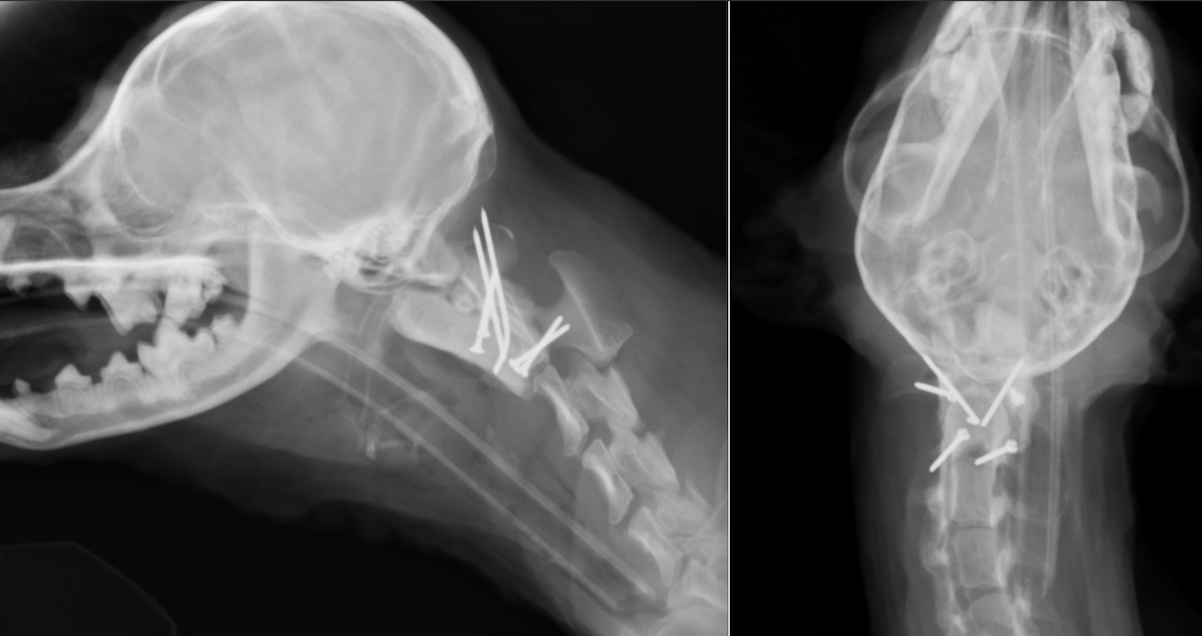

左がCT画像、右がMR画像です。2番めの頚椎である軸椎の歯突起が神経を圧迫してしまっているのがわかります。

治療には、経関節固定(1.1mmのピン)とスクリュー(1.3mm)・骨セメント(PMMA)による固定を行っています。

終了後のレントゲンです。

術後レントゲンです。8本のピンが刺入されているのが分かります。術後からとても経過はよく、1週間後には歩行可能となり、3ヶ月経過現在元気に歩き回っています。